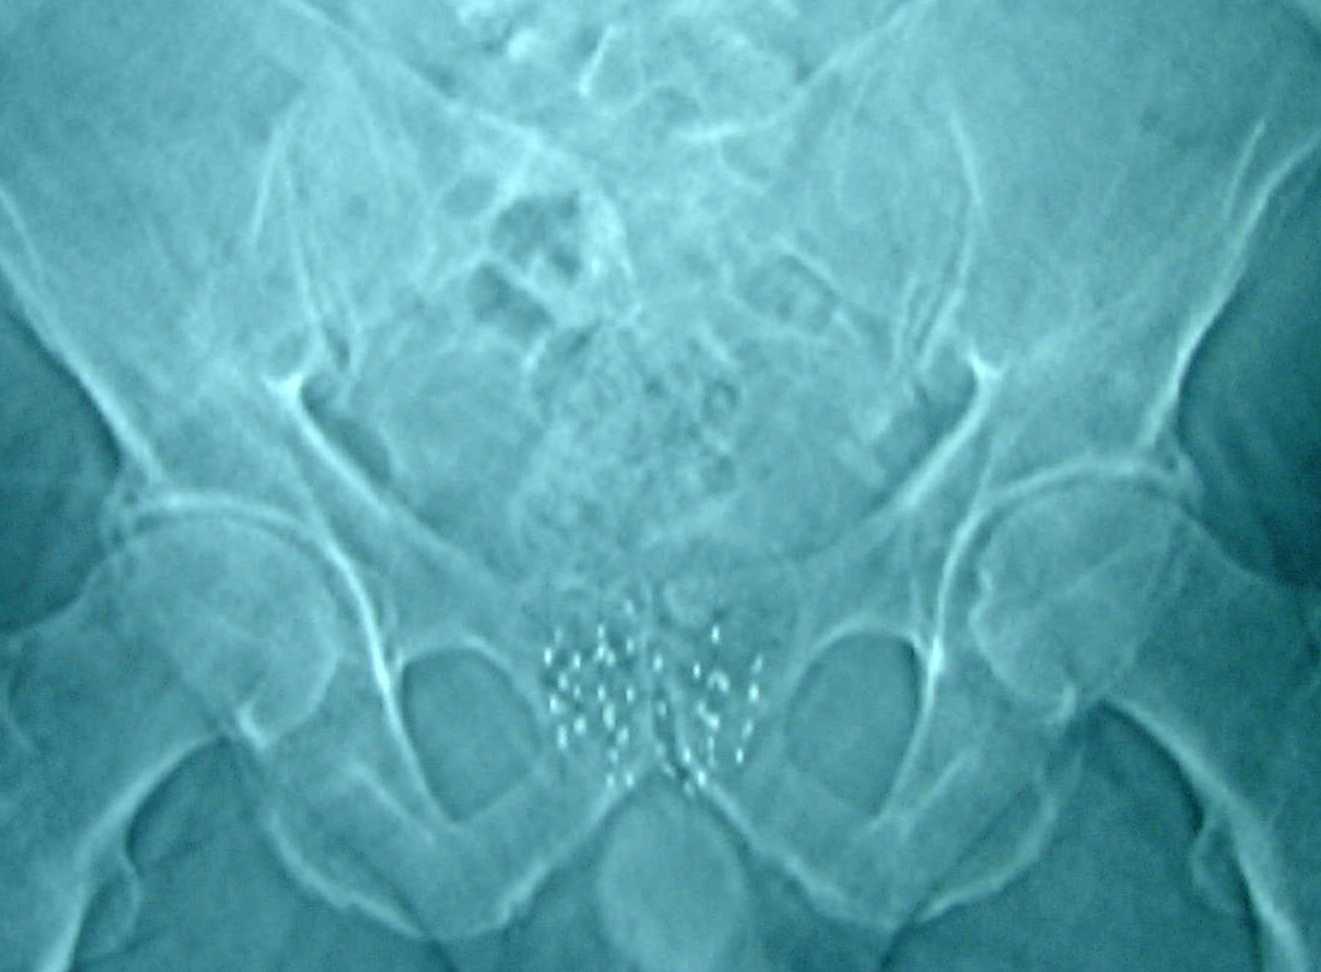

Röntgenfoto van het bekken met Jodium 125 zaadjes

De arts prikt met een naald via de huid tussen de balzak en de anus in de prostaat. Via de naald worden de zaadjes op de vooraf berekende plek in de prostaat gebracht en achtergelaten. De arts zal dit meerdere keren herhalen tot alle zaadjes in de prostaat zijn gebracht. Als alle zaadjes zijn ingebracht, wordt de blaaskatheter verwijderd.